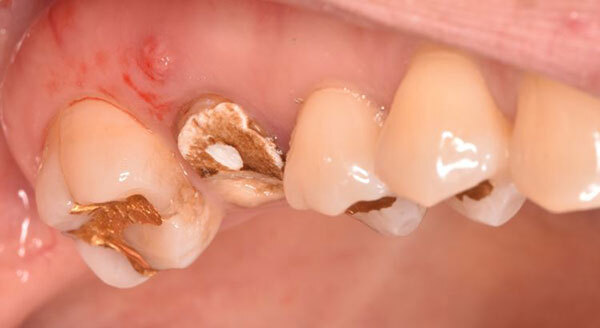

術前のデンタルX線写真と口腔内写真です。左下の一番奥の歯(#37)です。

親知らずと隣り合っていた歯の後ろ側(遠心)から虫歯が進行しています。

診査の結果、神経は正常に生きていることが分かりました。その為、いきなり神経は取らずに虫歯を取り切った上で神経を温存する治療を進めていくこととなりました。

虫歯を全て取り切ると神経が露出しました。